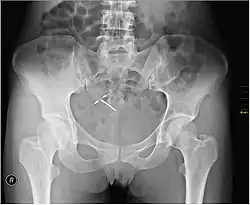

An intrauterine device (IUD), also known as an intrauterine contraceptive device (IUCD or ICD) or coil,[3] is a small, often T-shaped birth control device that is inserted into the uterus to prevent pregnancy. IUDs are a form of long-acting reversible contraception (LARC).[4]

Most copper IUDs have a T-shaped frame that is wound around with pure electrolytic copper wire and/or have copper collars (sleeves). The arms of the frame hold the IUD in place near the top of the uterus. The Paragard TCu 380a measures 32 mm (1.26") horizontally (top of the T), and 36 mm (1.42") vertically (leg of the T). Copper IUDs have a first-year failure rate ranging from 0.1 to 2.2%.[46] They work by damaging sperm and disrupting their motility so that they are not able to fertilize an egg. Specifically, copper acts as a spermicide within the uterus by increasing levels of copper ions, prostaglandins, and white blood cells within the uterine and tubal fluids.[6][47] The increased copper ions in the cervical mucus inhibit the sperm's motility and viability, preventing sperm from traveling through the cervical mucus, or destroying it as it passes through.[48] Copper can also alter the endometrial lining, and while studies show that this alteration can prevent implantation of a fertilized egg ("blastocyst"), it cannot disrupt one that has already been implanted.[49]